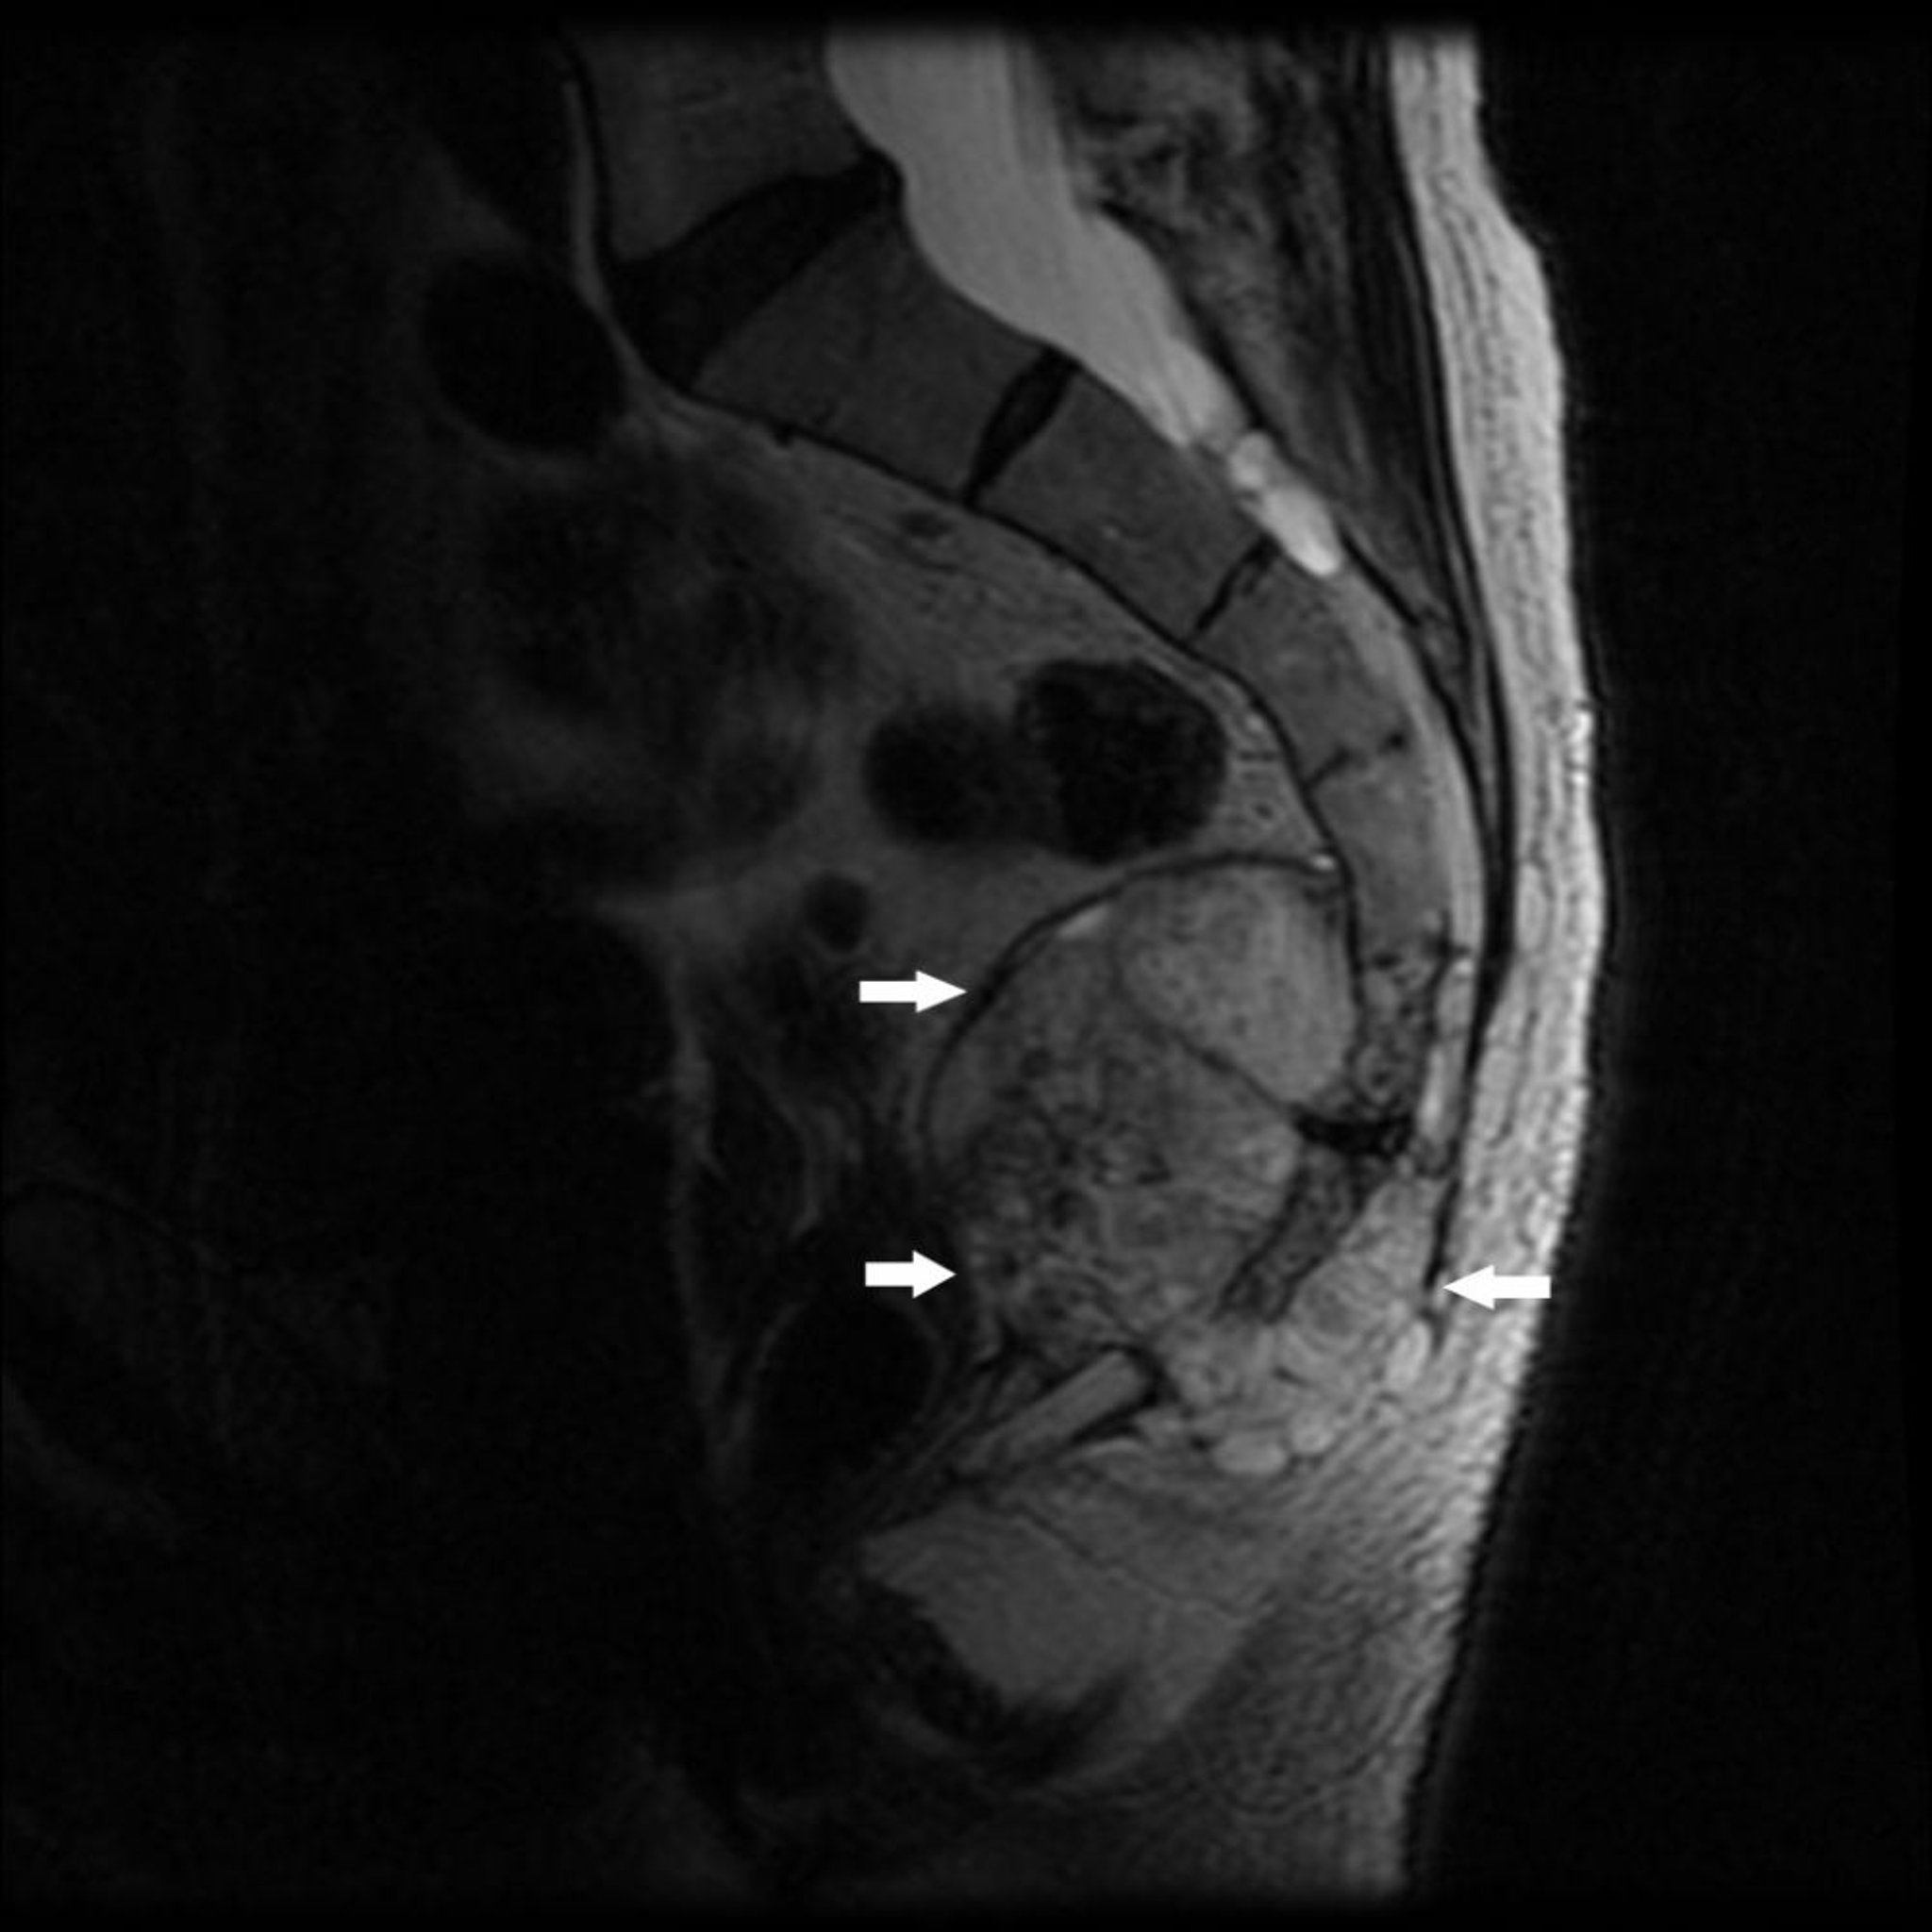

Phim MRI này cho thấy khối u ở phần đuôi xương cùng (S4) và xương cụt có tình trạng phá hủy xương và khối u ở mô mềm (mũi tên), đặc trưng của u nguyên sống.

Hình ảnh do bác sĩ Michael J. Joyce, và bác sĩ Hakan Ilaslan cung cấp.